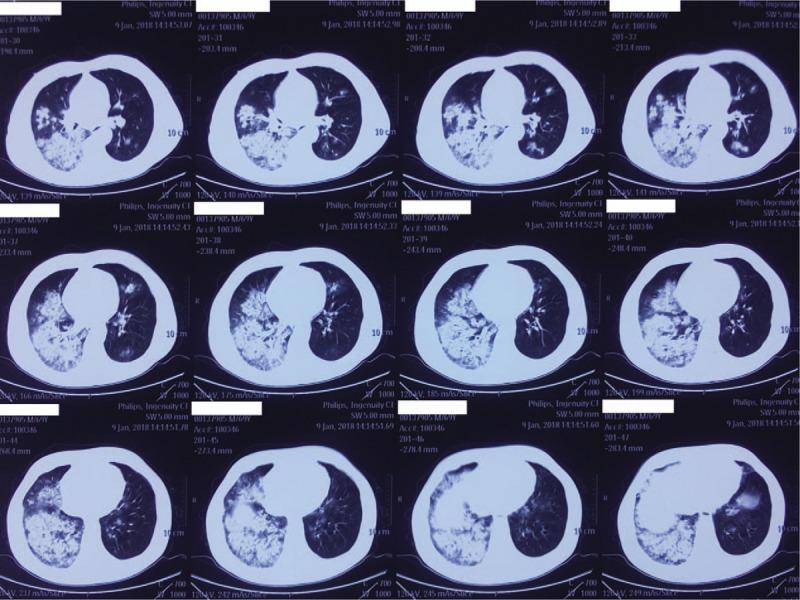

PATIENT CONCERNS

A 68-year-old male with no concerning medical history had developed a fever that reached 39.0°C, a productive cough that was sustained for 5 days, and hypodynamia. He was treated with azithromycin and alexipyretic in a nearby clinic for 2 days in which the symptoms were alleviated. However, 1 day later, the symptoms worsened, and he was taken to a local Chinese medicine hospital for traditional medicine treatment. However, his clinical condition deteriorated rapidly, and he then developed dyspnea and hemoptysis.

DIAGNOSIS

CA-MRSA pneumonia and septic shock. The sputum culture showed MRSA. Polymerase chain reaction of MRSA isolates was positive for PVL genes.